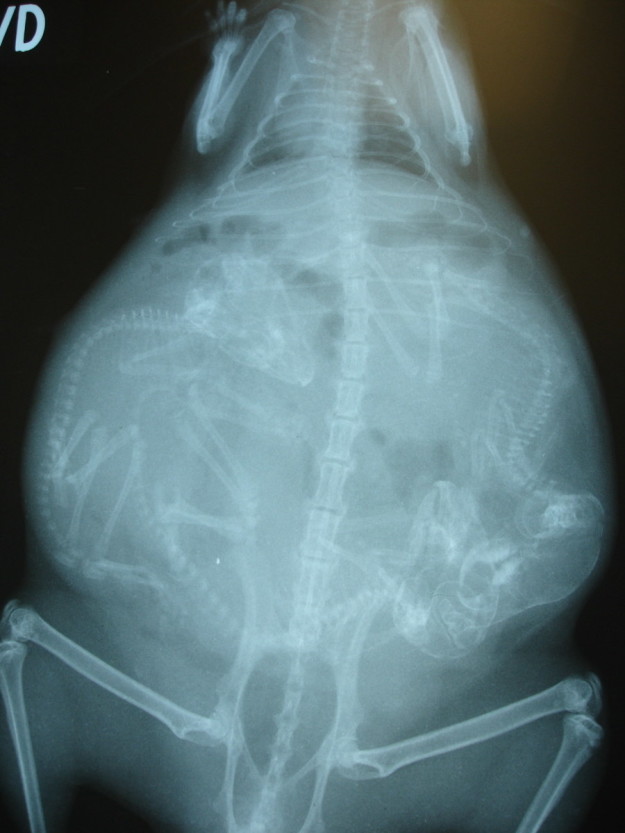

Беременная собака.